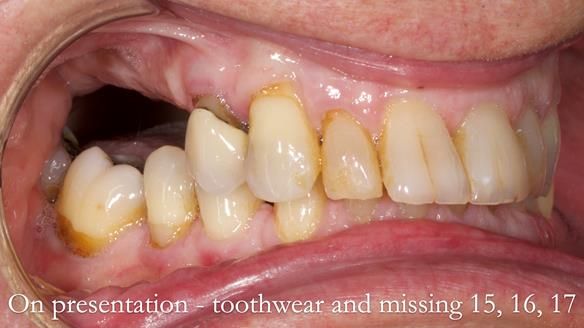

Welcome to Newsletter 64. I'll walk you through the process of providing a Mk 2 metal-based partial denture (RPD), for Ian a retired Veterinary Surgeon aged 78. The RPD was made at an increased vertical dimension and acted as an occlusal stabilisation splint - reducing the wear and bite force on the remaining natural teeth.

Ian was referred to me by his general dentist.